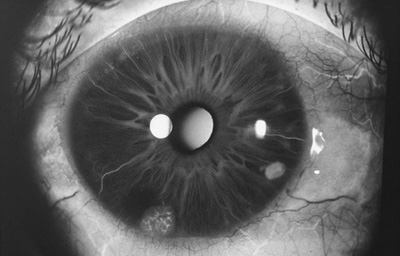

Melanocitomas

Melanocitoma es una lesión benigna, profundamente pigmentada, variante del, nevus uveal que fue originalmente descrito por Zimmerman y Garron en 1962 en el nervio óptico; ahora se sabe que puede aparecer en cualquier lugar del tracto uveal.

Son masas con algo de elevación, con pigmento marrón oscuro casi negro, frecuentemente con apariencia de “ montículo de arena negra”. Sus células son ovoides con núcleos uniformes, pequeños y muy pigmentados. pueden generar satélites en el estroma o en el ángulo de la cámara anterior. Pueden evolucionar a Melanoma (30)

Aniridia

Archivo Fotográfico Dr. Francisco Barraquer. 2012

Nevus con escaso pigmento

Archivo Fotográfico Dr. Francisco Barraquer. 2017

Estudio comparativo